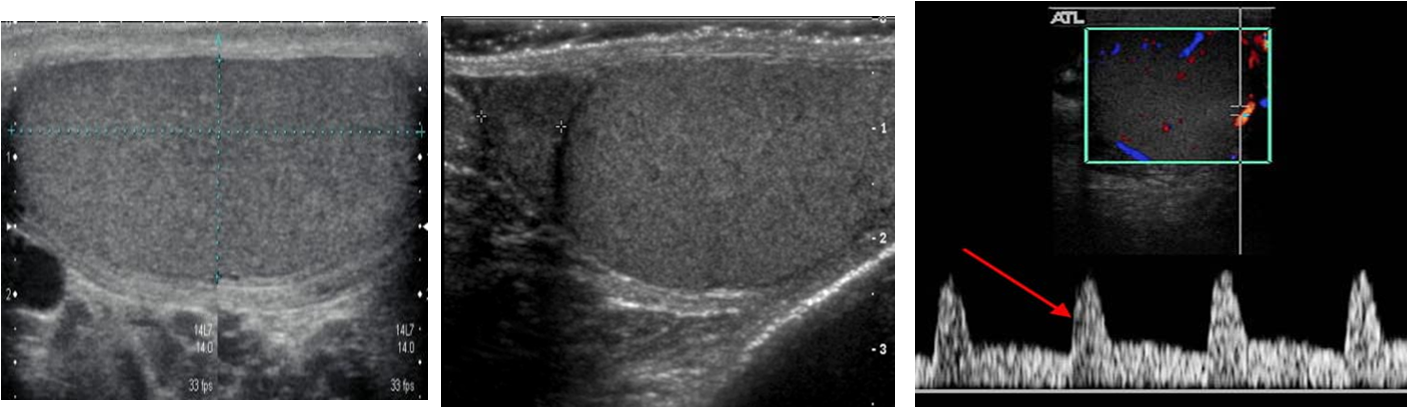

The addition of color Doppler sonography prov ides simultaneous display of morphology and blood flow.

Normal intratesticular arterial blood flow is consistently detected with power or ***color Doppler ***